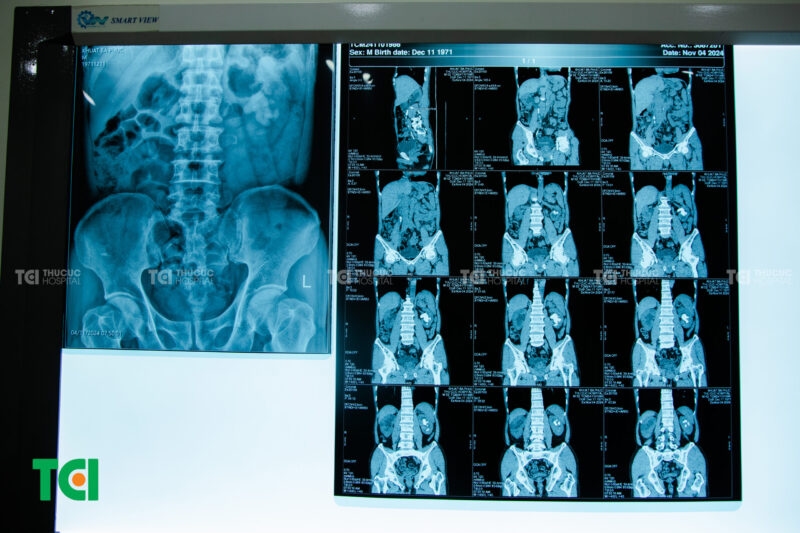

Trường hợp bệnh nhân mắc sỏi tiết niệu đa vị trí của TCI (sỏi thận phải, nhiều sỏi niệu quản phải, sỏi san hô thận trái, sỏi đài thận trái)